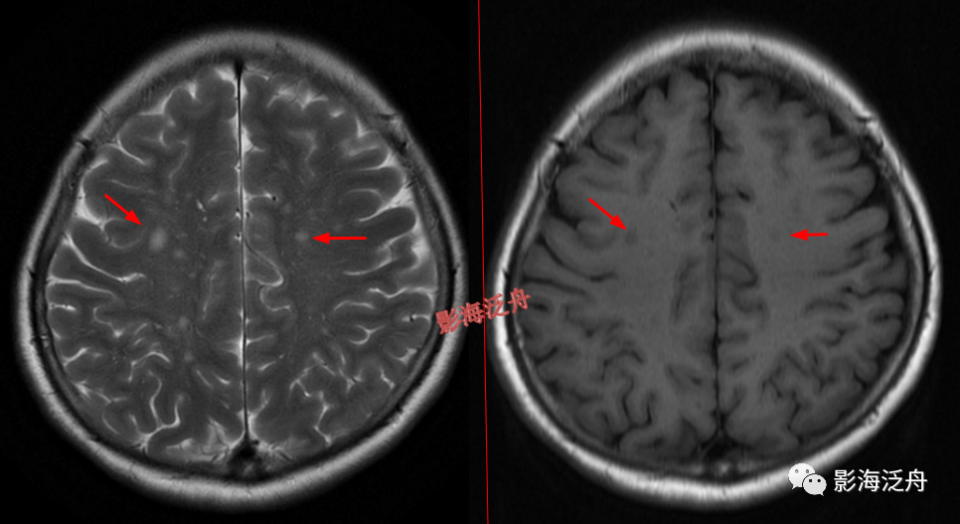

当脱髓鞘改变呈片状且沿着侧脑室周围对称性分布时,大家往往一眼就能识别出来,像上图这种双侧半卵圆中心多发非特异性脱髓鞘病灶,大家可能就有点心虚了。注意最大的一个病灶(黄箭)长轴平行于侧脑室(红线),所以只是普通的退变,而不是不是MS。

当这种非特异性脱髓鞘病灶比较局限、散发的时候,如何与VR腔隙及腔梗灶区分呢?一般来说,前者显示比后两者更加浅淡和模糊,在T1WI序列尤为明显。